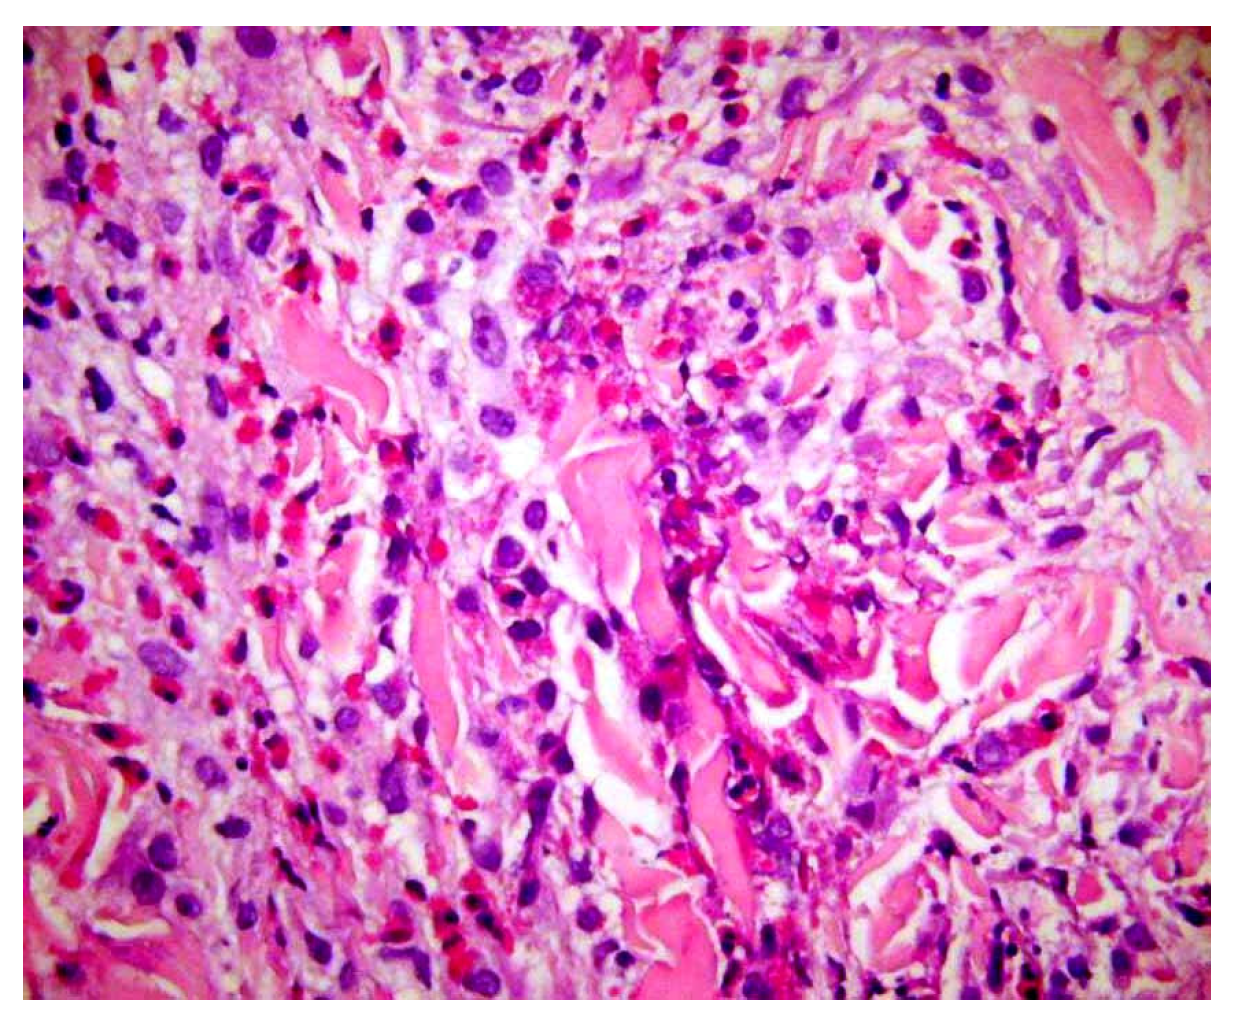

Base rates: When two hypotheses explain the finding equally well, the more common disease in the given setting (season, geography, clinic type) is preferred. However, always keep a rare “zebra” on the list if missing it would be catastrophic. For example, an atypical erythema multiforme-like eruption with a tendency to ulcerate may represent a primary cutaneous aggressive epidermotropic CD8+ cytotoxic T-cell lymphoma (Figure 2).

Figure 2.

(A) Primary cutaneous aggressive epidermotropic CD8+ cytotoxic T-cell lymphoma presenting with large, targetoid, partly ulcerated plaques resembling atypical erythema multiforme. (B) Vacuolar and lichenoid interface dermatitis-like changes. The condition was initially misinterpreted as atypical erythema multiforme, leading to diagnostic delay with a catastrophic outcome.